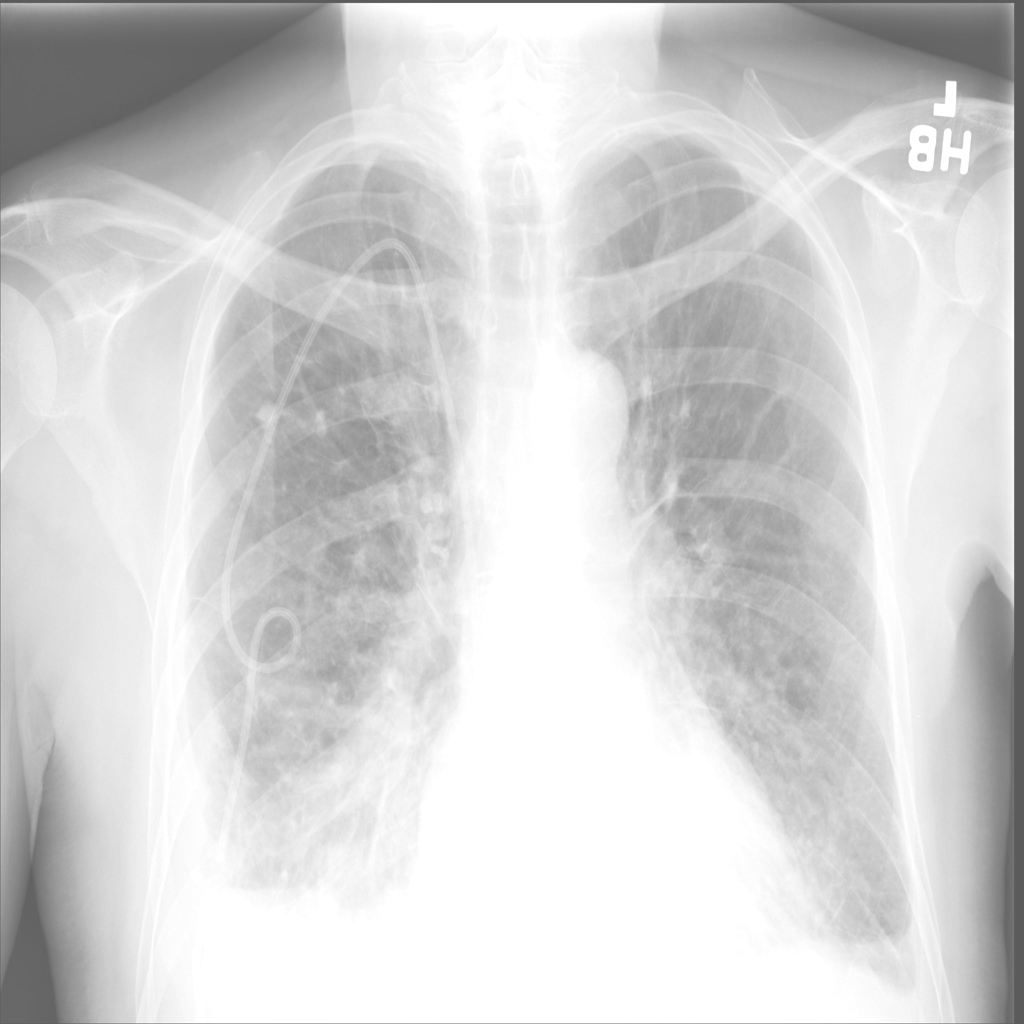

🔬 Medical Imaging Modalities

Eight different medical imaging modalities supported by UniMedVL

Chest X-ray

Chest X-ray (CXR)